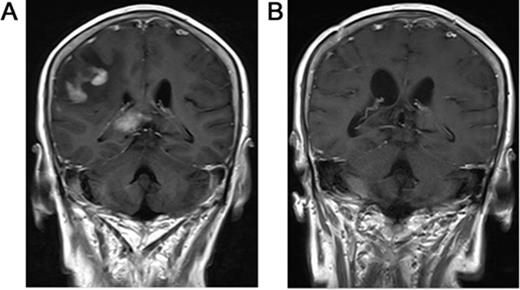

T1 axial, post-gadolinium magnetic resonance imaging of PCNSL.